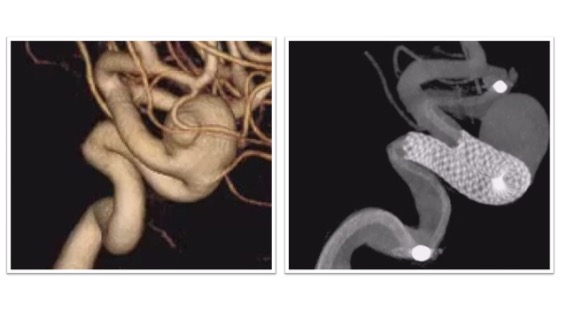

フローダイバーター治療実例(*患者様の許可を得て掲載しています)

大型内頸動脈(IC)動脈瘤

大型IC動脈瘤に対してフローダイバーターによる治療を実施。フローダイバーターは動脈瘤の根本をカバーする形で留置されました(右図)。術後は抗血小板薬の内服がしばらく必要となりますが、動脈瘤はその後半年ほどで閉塞しています。